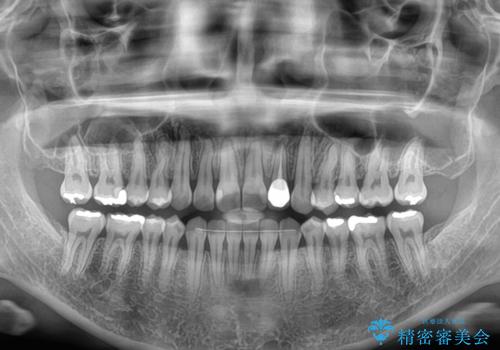

開咬と変色した前歯 インビザライン矯正とオールセラミッククラウン治療

矯正治療が概ね終了した時点で前歯をオールセラミッククラウンにて補綴治療を行い、その後インビザラインにて細かい部分を仕上げていくことしました。

オープンバイトは舌の突出癖により誘発され、治療後も突出癖が残っている容易に後戻りしてしまいます。

治療期間を短縮するためにも、舌突出癖の改善が極めて重要となります。